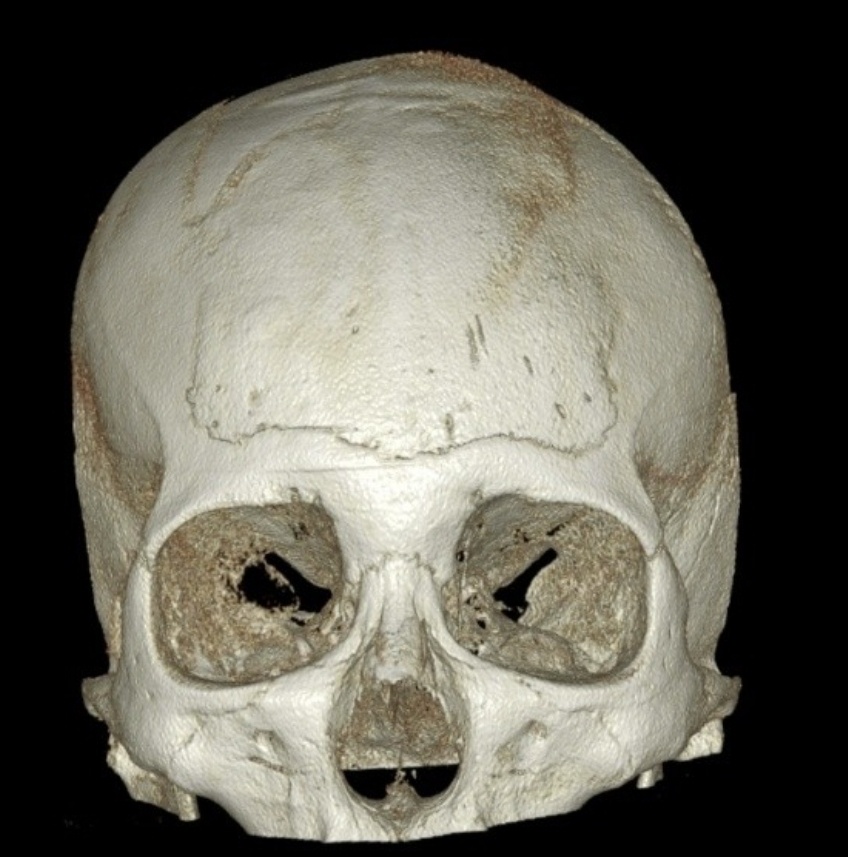

10년전 수술한 메틸본드 이마 성형 씨티사진 입니다.

0사진에서 보신것처럼 메틸본드를 제거하고 거상술을 받아도 눈썹위로?? 저런 볼륨이나

형태가 생기나요?? 아니면 메틸본드로 인한 것인지 궁금합니다.